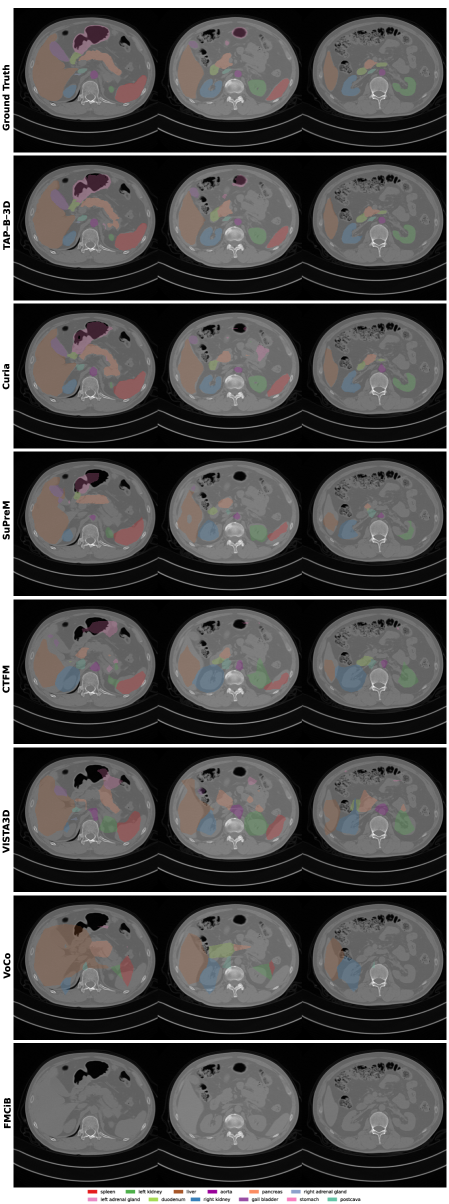

We show several abdominal CT slices with segmentation masks of the AMOS downstream task in Figure 4.

Refer to caption

Figure 4: Segmentations across three abdominal slices from the AMOS22 validation sample (amos_286) for TAP-B-3D and other publicly available pretrained FMs. Each segmentation is produced using a linear convolutional layer fine-tuned on top of the frozen features of the respective pretrained encoder.